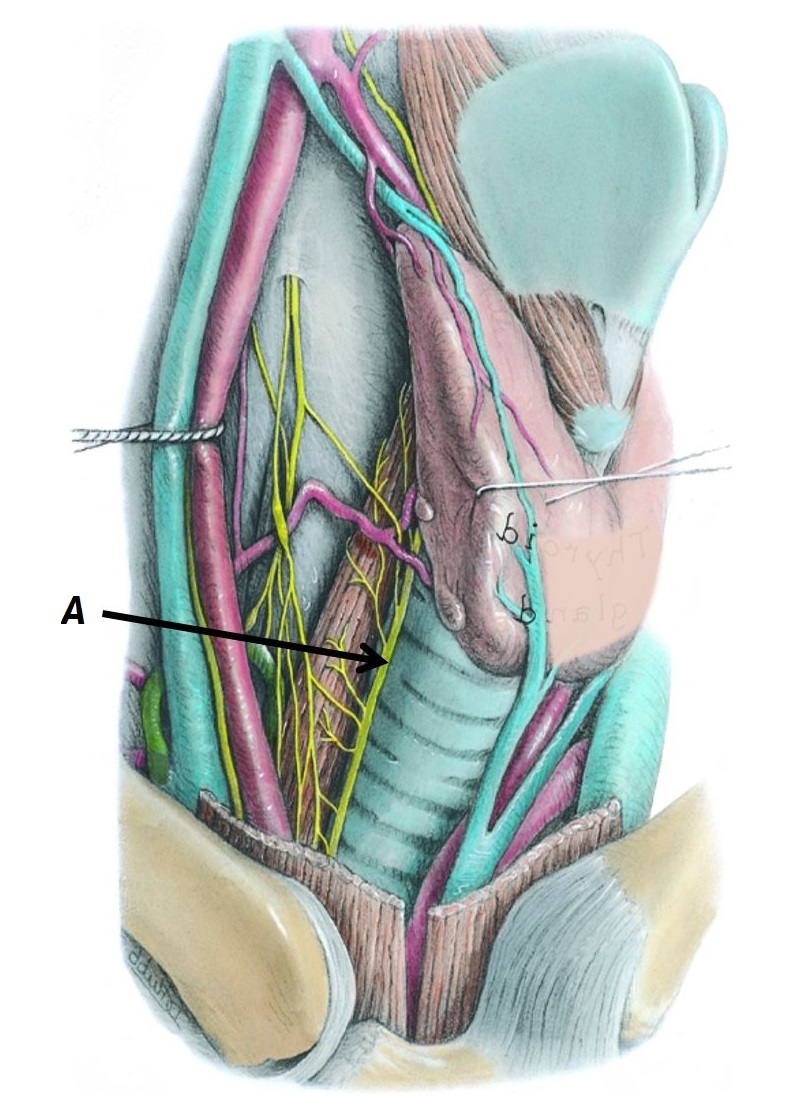

Name nerve A

A - Right recurrent laryngeal nerve